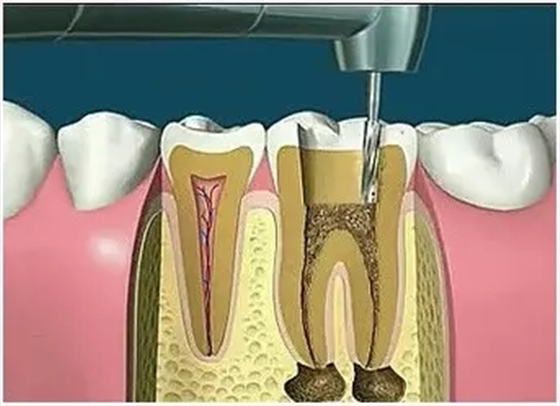

2、揭開髓腔

去凈腐質(zhì)和原有充填物、揭凈隨頂,看到整個(gè)髓底解剖結(jié)構(gòu)以便后續(xù)治療順利進(jìn)行。